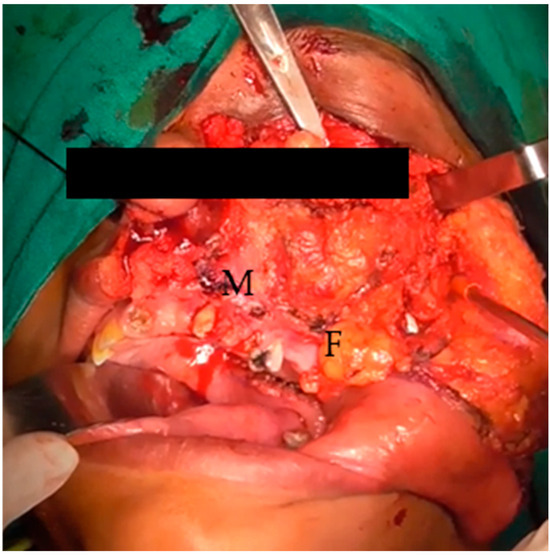

Figure 2.

Elevated cheek flap, exposed maxilla (M), and buccal fat (F).